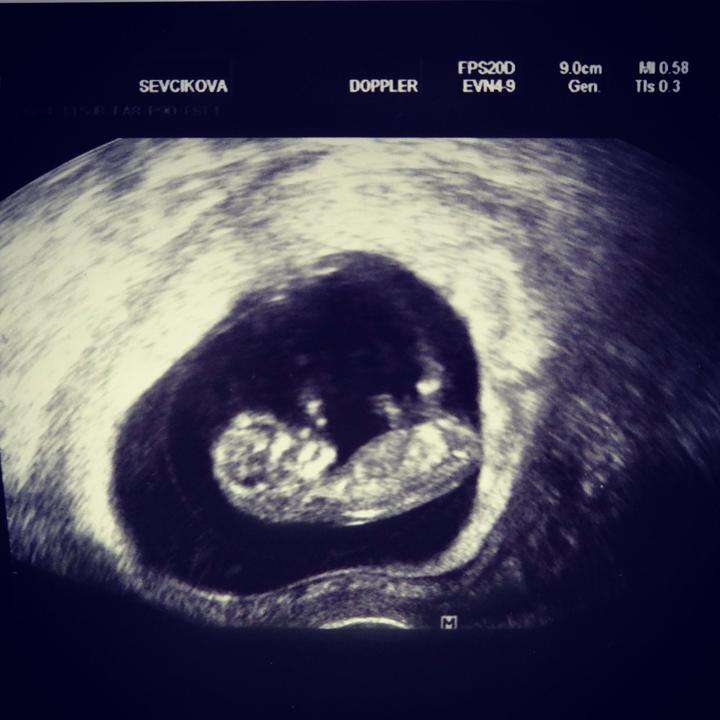

Tak dnes jsem poprvé slyšela tlouct srdíčko toho našeho zázraku milovaného 🙂 Krásně nám roste od 5+3tt nyní jsem 8+1t obrovský skok.

Nase prvni fotecka z ultrazvuku 🙂 5+3tt